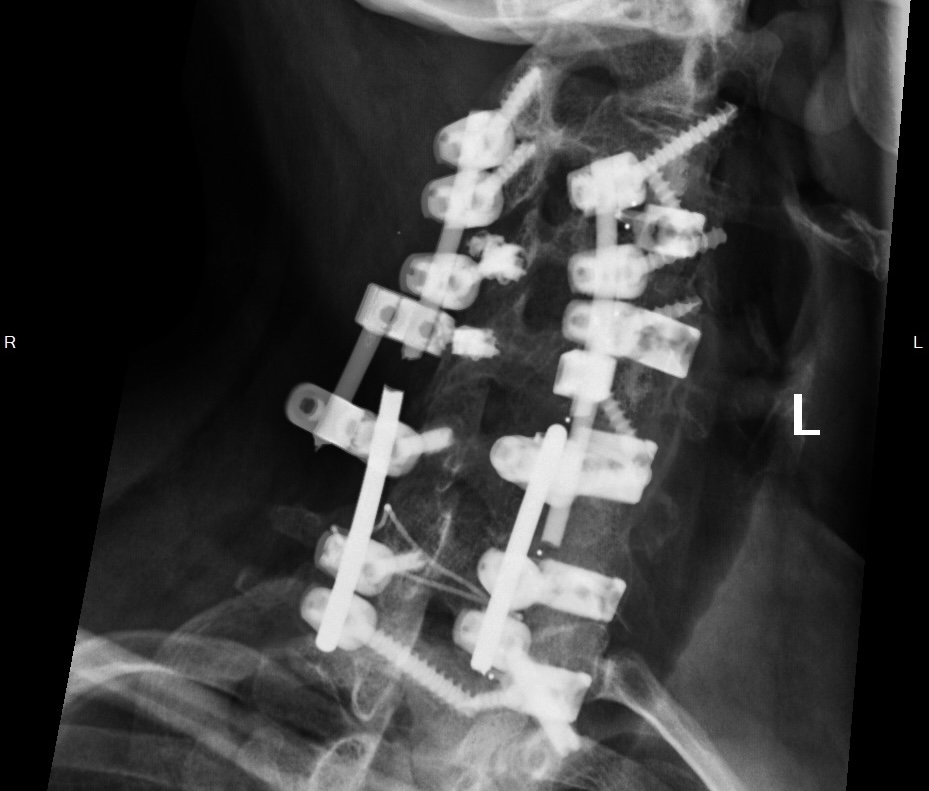

"You need a cervical fusion," he said. "We'll remove the damaged disc, insert a titanium cage packed with bone graft, and secure it with plates and screws."

I remember staring at the X-ray images. At the shattered disc that looked like a crushed grape between my vertebrae.

Four weeks later, I woke up from surgery with a 3-inch incision in my throat and hardware permanently fused into my spine.

X-rays of patients - including post-fusion patients - using a pillow with something called "Nanocoil fiber technology."

The cervical alignment was perfect. Maintained through full 8-hour sleep cycles.

"We've documented patients with cervical hardware reporting 70% or greater reduction in morning pain," he said. "Including multi-level fusions."